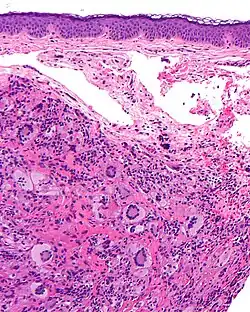

Die Histiozytosen sind eine heterogene Gruppe seltener Erkrankungen mit tumorähnlichen Läsionen, die durch eine abnorm hohe Zahl (Proliferation) an histiozytären Zellen charakterisiert sind.[1]